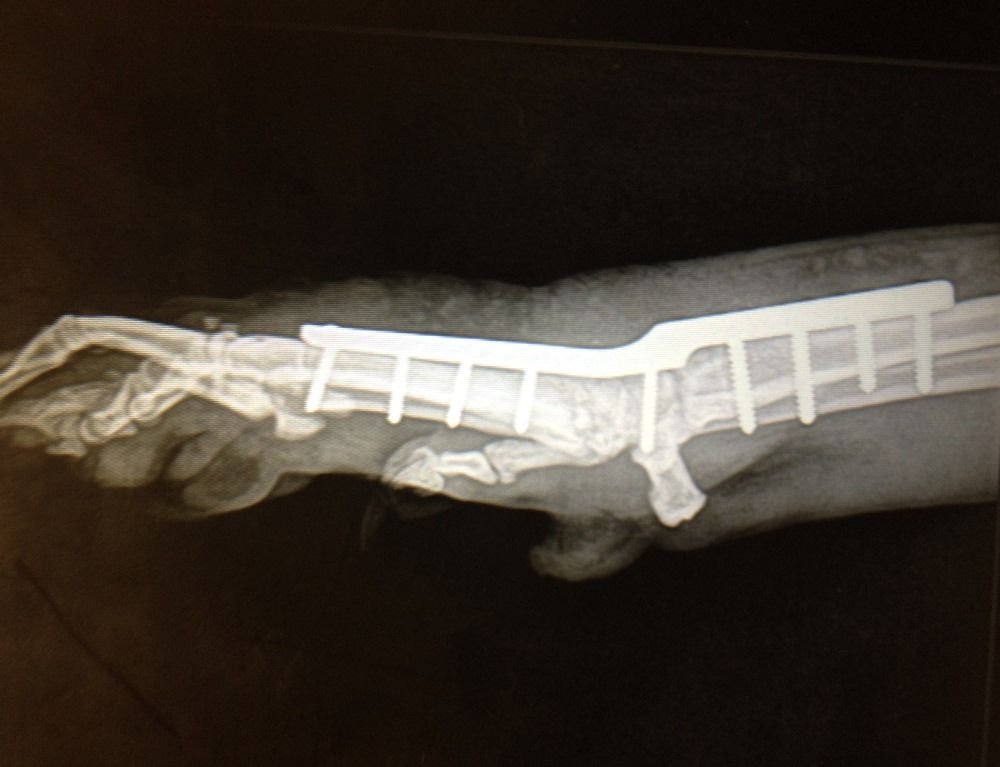

TPLO

La TPLO (Tibial Plateau Levelling Osteotomy) y la TWO (tibial wedge ostectomy) son otras técnicas de resolución de rotura de ligamento cruzado muy eficaces en perros de gran talla.

Consiste en hacer un corte en la tibia y nivelar la meseta tibial, aplicando una placa especial que hace que el ligamento cruzado no sea necesario, ya que se neutralizan la fuerzas de empuje tibial.